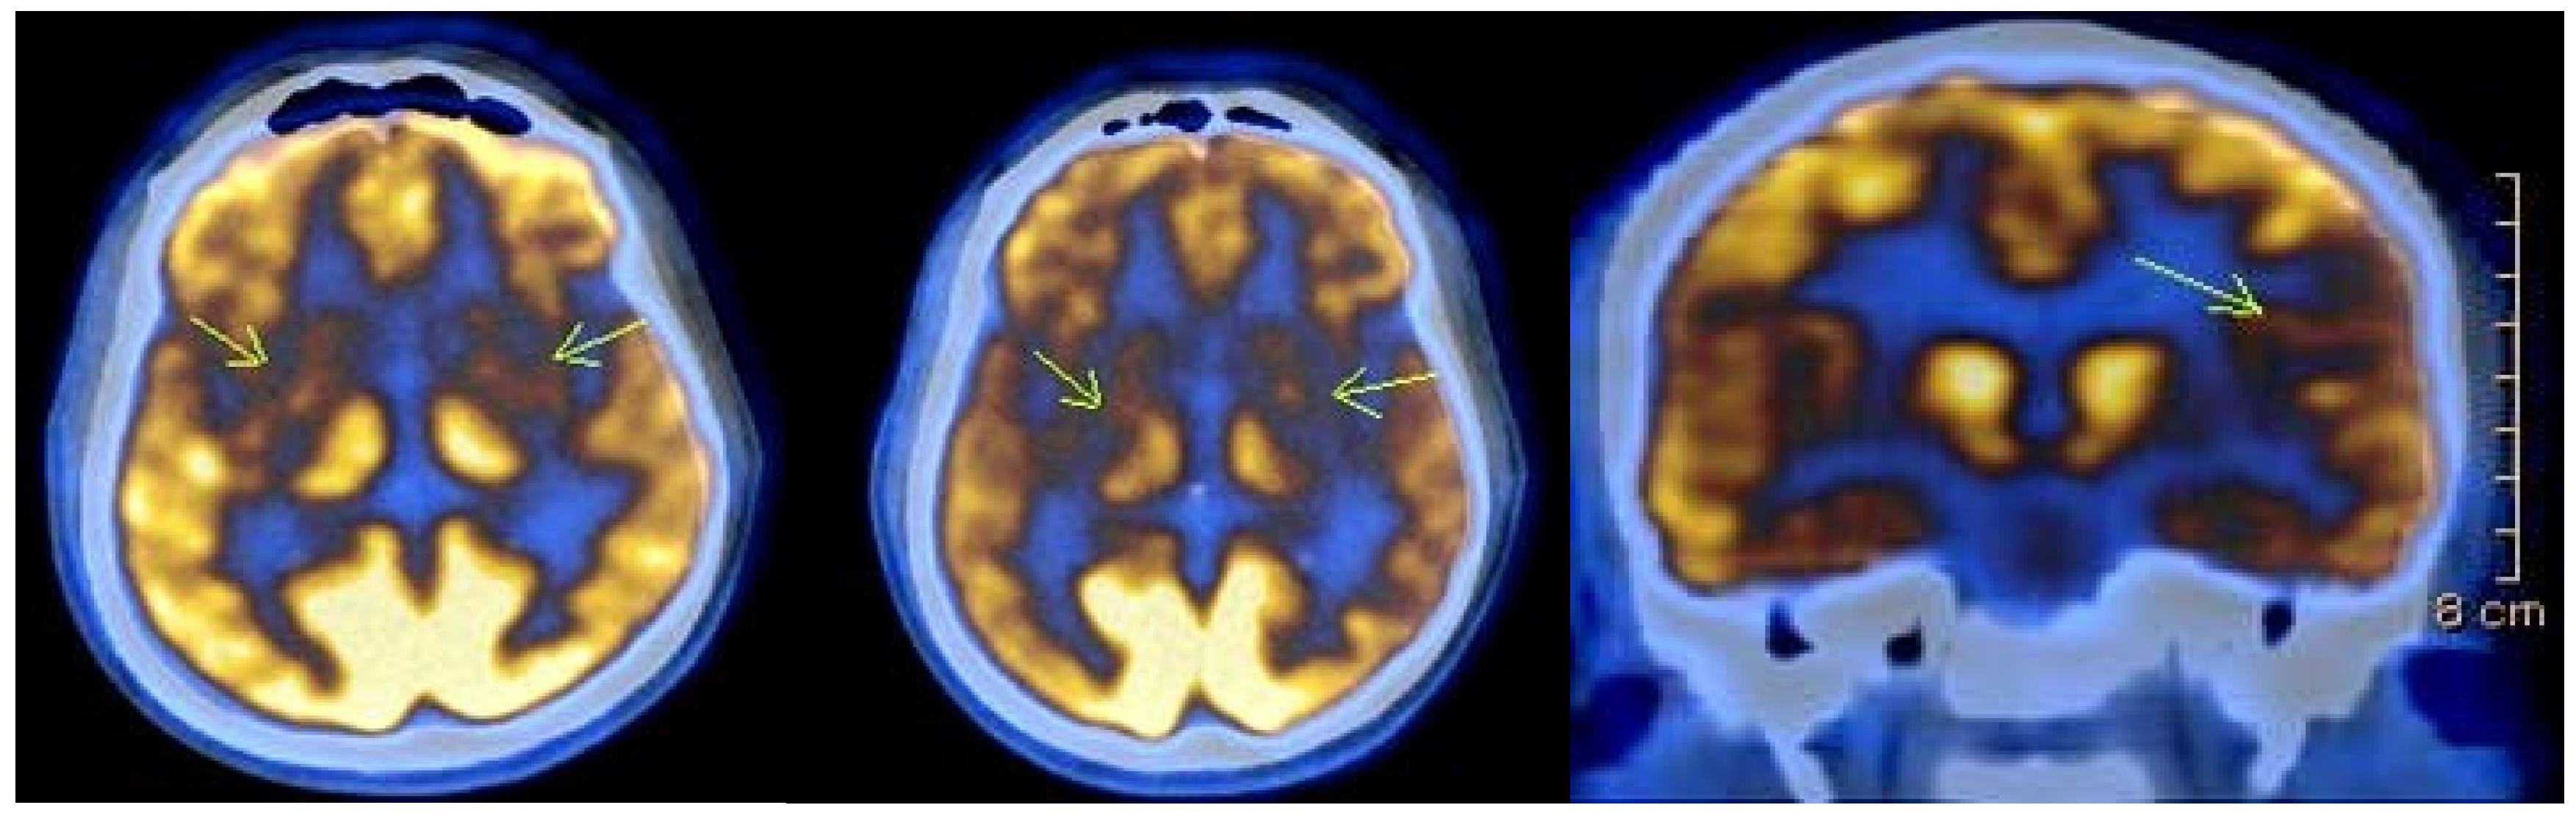

Imaging studies were conducted in 27 individuals, and revealed typical findings, including atrophy of the caudate nucleus and cortical atrophy in most patients. Eight of the affected individuals underwent Fluorine-18 Fluorodeoxyglucose Positron Emission Tomography (18)F-FDG PET) as part of a separate ongoing research project. In seven of them (87.5%), the scans revealed areas of significantly reduced or absent metabolic activity in the caudate nucleus and putamen bilaterally. Additionally, cortical hypometabolism was observed in 50% of cases in the left superior parietal region, in 37.5% of cases in the right superior parietal region, and in 12.5% of cases in the left superior and inferior frontal regions. One of the patients was followed up after one year, and the results showed further reduction to absence of metabolic activity bilaterally in the striatum, as well as in the left temporoparietal region (Figure 2).

Figure 2. (18)F-FDG PET images of a 35-year-old patient with Huntington’s disease showing severely reduced to absent metabolic activity (indicated with arrows) bilaterally in the striatum. A follow-up scan one year later revealed additional hypometabolism (indicated with arrows) in the left temporoparietal region. Imaging was obtained as part of routine clinical care, and detailed acquisition parameters (e.g., isotope dose and time post-injection) were not available due to the retrospective nature of the data.